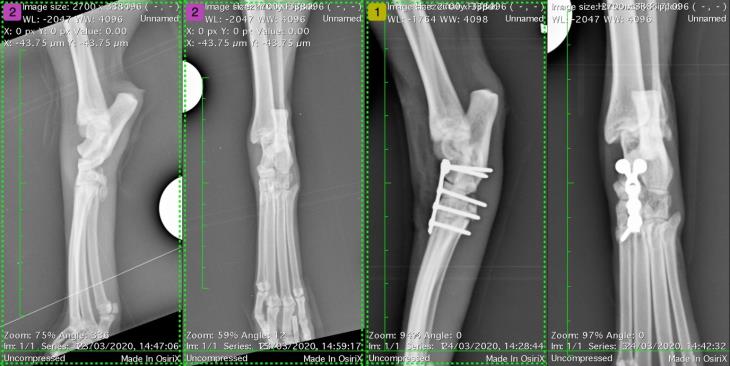

When he arrived at Eastcott Referrals his right thoracic limb lameness and humeral fracture were visually evident from a distance. Despite Max walking remarkably well on his remaining three limbs, full orthopaedic assessment showed pain and dorsal instability of the left tarsus too. Radiographs were taken for full assessment and showed a proximal humeral physeal fracture.

Max underwent surgery to repair his physeal fracture with pins and a tension band. A dorsal mini plate was placed across the dorsal tarsus with two screws in the talus, one in the central tarsal bone, one in the third tarsal bone and one in the very proximal second metatarsal bone.